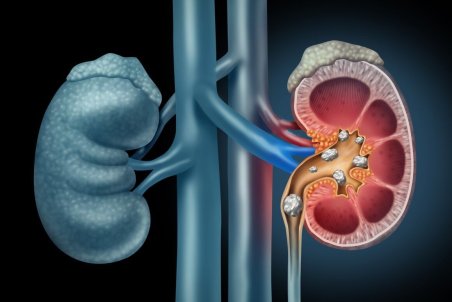

سنگ کلیه جسم سختی است که از موادشیمیایی در ادرار تشکیل شده. انواع متعددی دارد،اما همه دارای علائم مشابهی هستند که می تواند بسیار دردناک باشند،به ویژه اگر سنگ کلیه به مرور زمان رشد کرده باشد.

یک فوق تخصص بیماریهای کلیه عوامل خطر ایجاد سنگ کلیه در افراد، بدون علامت بودن سنگها، وجود دردهای شدید در کلیه، راههای پیشگیری و توصیههای تغذیهای برای جلوگیری از بروز از سنگ سازیهای بعدی در کلیه را تشریح کرد.

فوق تخصص کلیه و نفرولوژی بزرگسالان گفت: تب و لرز، سوزش، بوی بد، تکرر و تغییر رنگ ادرار، سوزش و درد در کلیهها از علائم عفونت ناشی از سنگ کلیه است.